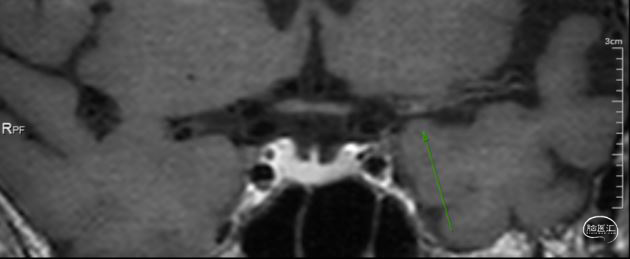

➢ 头颅高分辨磁共振

管壁高分辨磁共振提示闭塞段斑块有强化,闭塞段不长。